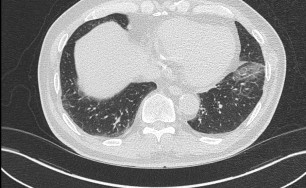

이러한 면역체계의 과민 반응이 기관지에 생기면 기관지벽이 두꺼워지고 그로 인해서 직경이 좁아지게 됩니다.

즉 천식은 기도 통로가 좁아지면 공기가 원활하게 지나가지 못하므로 호흡이 어려워져서 기침, 천식음(쌕쌕 거리는 소리), 호흡곤란, 가슴답답 등이 반복적으로 발생하는 질환입니다.